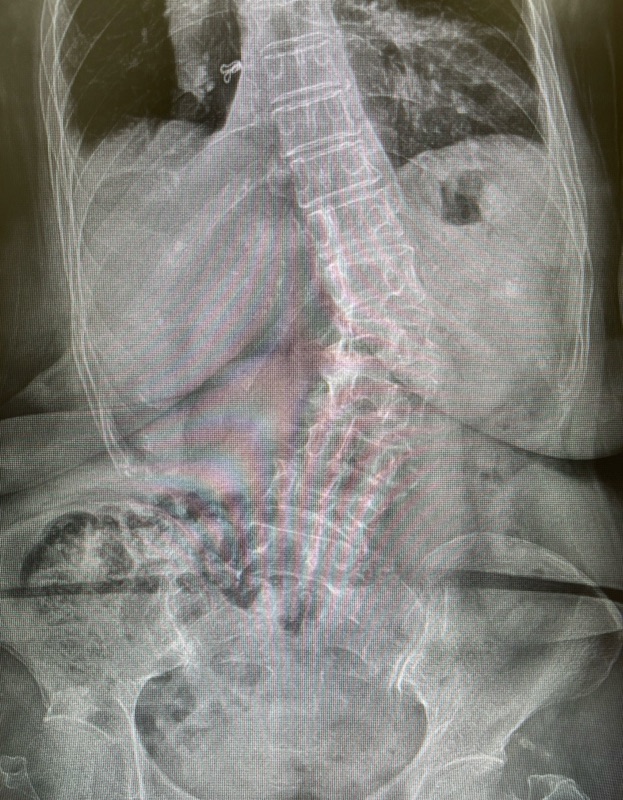

✔ 1) X-ray ยืนทั้งสันหลัง

เพื่อดูองศาการคด (Cobb angle) และลักษณะของกระดูกผิดรูป